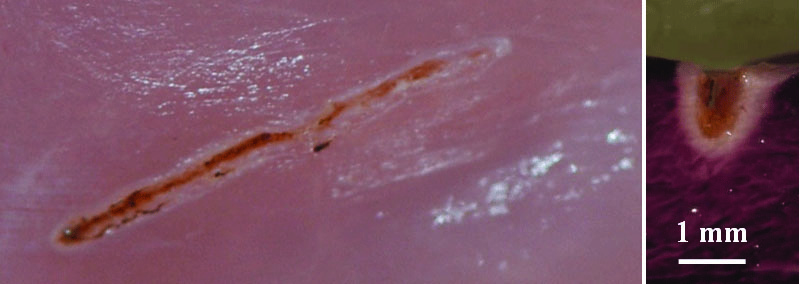

The images shown in Figure 7 and Figure 8 represent a series of photos (top row) and histology (bottom row) of soft-tissue cutting at five different speeds of movement, ranging from 12.5 mm per second to 0 mm per second (stop for several seconds) performed with a traditional diode laser using fixed power (Figure 7) and TOP surgery with automatic power control (Figure 8).13 These experiments were performed using a translation stage with programmable speed and controlled vertical force between the fiber and the sample. To visualize tissue damage, nitro blue tetrazolium chloride (NBTC) viability staining was used, so stained areas show live cells, while cells in white areas are dead. This stain became a standard tool to visualize tissue thermal damage in laser surgery.16,17 It is characteristic that when the speed decreases, the cutting depth and level of collateral tissue damage and carbonization increase sharply for diode lasers, but they remain essentially the same with the new laser technology. The histological evaluations (Figure 7 and Figure 8) illustrate how the influence of cutting speed can reduce tissue damage with automated power control.

Fig 7. NBTC stain showing effect of cutting speed on collateral thermal damage using

regular diode laser.

Figure 7